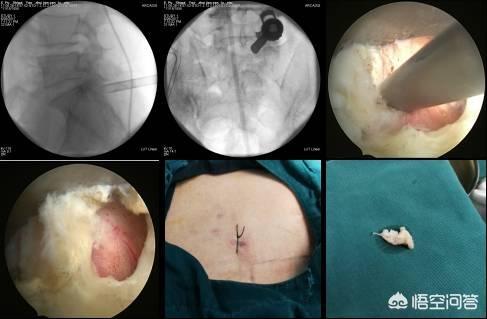

La chirurgie de la hernie discale lombaire se divise aujourd'hui en deux catégories : la chirurgie mini-invasive et la chirurgie ouverte. Les deux premiers types de chirurgie sont davantage pratiqués dans le service de la douleur, ce qui est moins traumatisant et permet une guérison plus rapide, mais uniquement pour les petits cas de hernie discale et, d'après l'expérience passée, l'effet de soulagement de la douleur est encore très bon au moment de l'apparition de la douleur aiguë.

La thermocoagulation par radiofréquence utilise une aiguille de radiofréquence de 0,7 mm de diamètre, qui est ponctionnée sous guidage par arceau ou tomodensitométrie, atteint avec précision le disque malade et active la thermocoagulation. Elle s'appuie sur le rayonnement thermique pour réduire la taille du nucleus pulposus hernié et soulager la compression des racines nerveuses. La différence entre la chirurgie au plasma et la thermocoagulation par radiofréquence est que cette dernière vaporise directement le tissu du nucleus pulposus hernié.

L'incision de la chirurgie du diamètre du foramen intervertébral est petite, généralement d'environ 7 mm, sans détruire les muscles et les ligaments paravertébraux, avec moins de saignements, sans effet sur la stabilité de la colonne vertébrale, et le symptôme de la douleur est soulagé rapidement grâce à l'élimination de la compression nerveuse après l'opération. La chirurgie ouverte s'adresse aux patients présentant une hernie discale lombaire accompagnée d'une dégénérescence vertébrale lombaire, d'ostéophytes, d'une sténose spinale et d'une sténose du canal de la racine nerveuse, d'une calcification ligamentaire, ainsi qu'aux patients présentant une instabilité évidente de la colonne vertébrale lombaire.